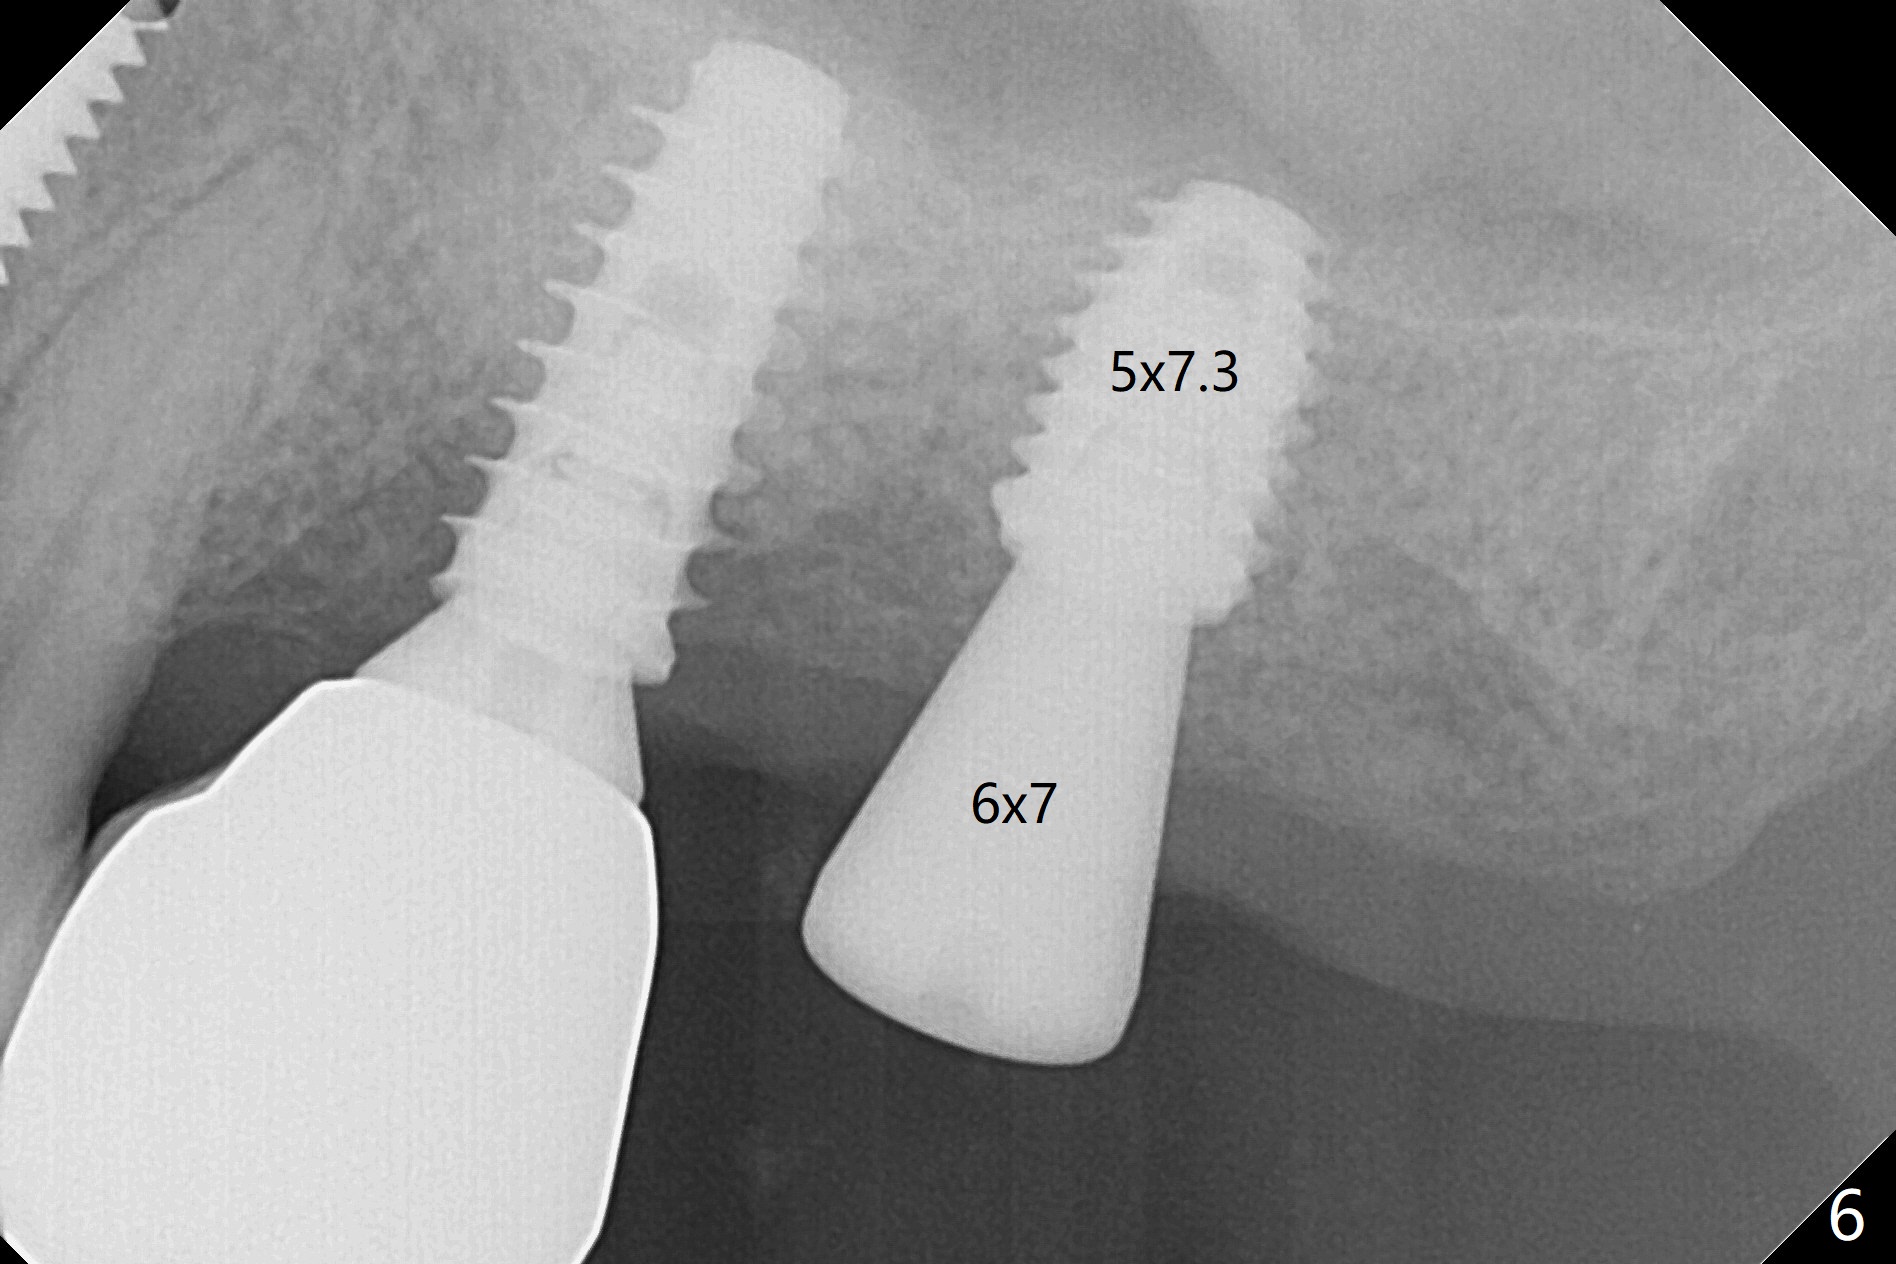

Today schedule is to extract the teeth #4 and 5 and place an implant at #5. When the latter is done, it appears that the implant at #15 should be placed at the same appointment (Fig.1). Once an abutment is placed at #5 (Fig.2 A, 5) for temporary crown (Fig.4 T) , the guide may be not seated again unless the crown is removed. Luckily the implant placement at #15 is quick and smooth with the guide (Fig.3,6). The implants seem to be covered by the bone 4 months postop (Fig.7,8). #15 abutment screw needs retightening because of long crown 1.5 months post cementation. Access hole is palatal. There is premature contact in lateral movement. The buccolingual occlusal table is large at #14 and 15. In fact there is more occlusal contact at #14 than #15 in centric occlusion. Tissue level implants should have been placed to reduce implant/abutment loosening. The incomplete abutment seating (Fig.5,7) is noted after retightening the loose cantilever FPD 1 year post cementation (Fig.9 <). After removal of the FPD, the abutment is reseated completely without interference of the proximal contacts (Fig.10).